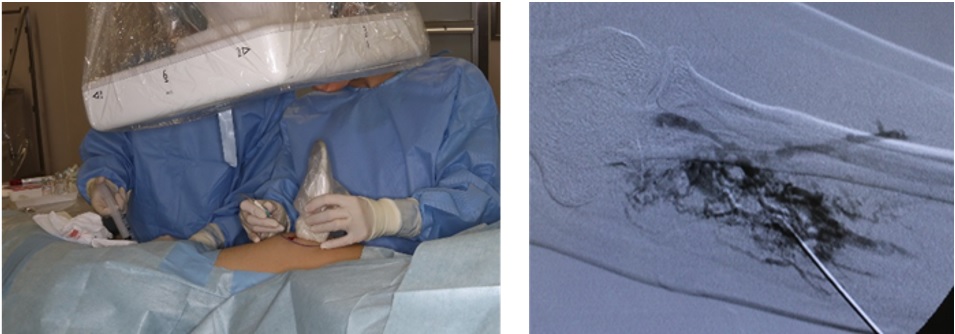

まず、治療に使われる薬剤「モノエタノールアミンオレイン酸塩(オルダミン®)」が、2024(令和6)年12月27日に薬事承認を受けました。多くの医療機関が協力して行った医師主導治験により、この薬剤が静脈奇形に対して有効で安全に使えることが証明されました。

薬事承認を受けたあと、尾崎教授らは形成外科だけでなく、放射線科、心臓血管外科、小児外科など、この治療に関わるさまざまな診療科とともに、硬化療法そのものを保険診療として認めてもらうための準備を進めました。全国から手術データを集め、外保連試案への掲載を経て、厚生労働省に医療技術評価提案書を提出しました。

静脈奇形は、痛みや腫れ、機能障害など生活の質を大きく損なう疾患であるにもかかわらず、これまで硬化療法は保険適用外であったため、最善の治療であっても受けられない患者さんが少なくありませんでした。今回の保険収載により、治療へのアクセスが大きく改善され、国内において標準的な治療として提供できるようになります。